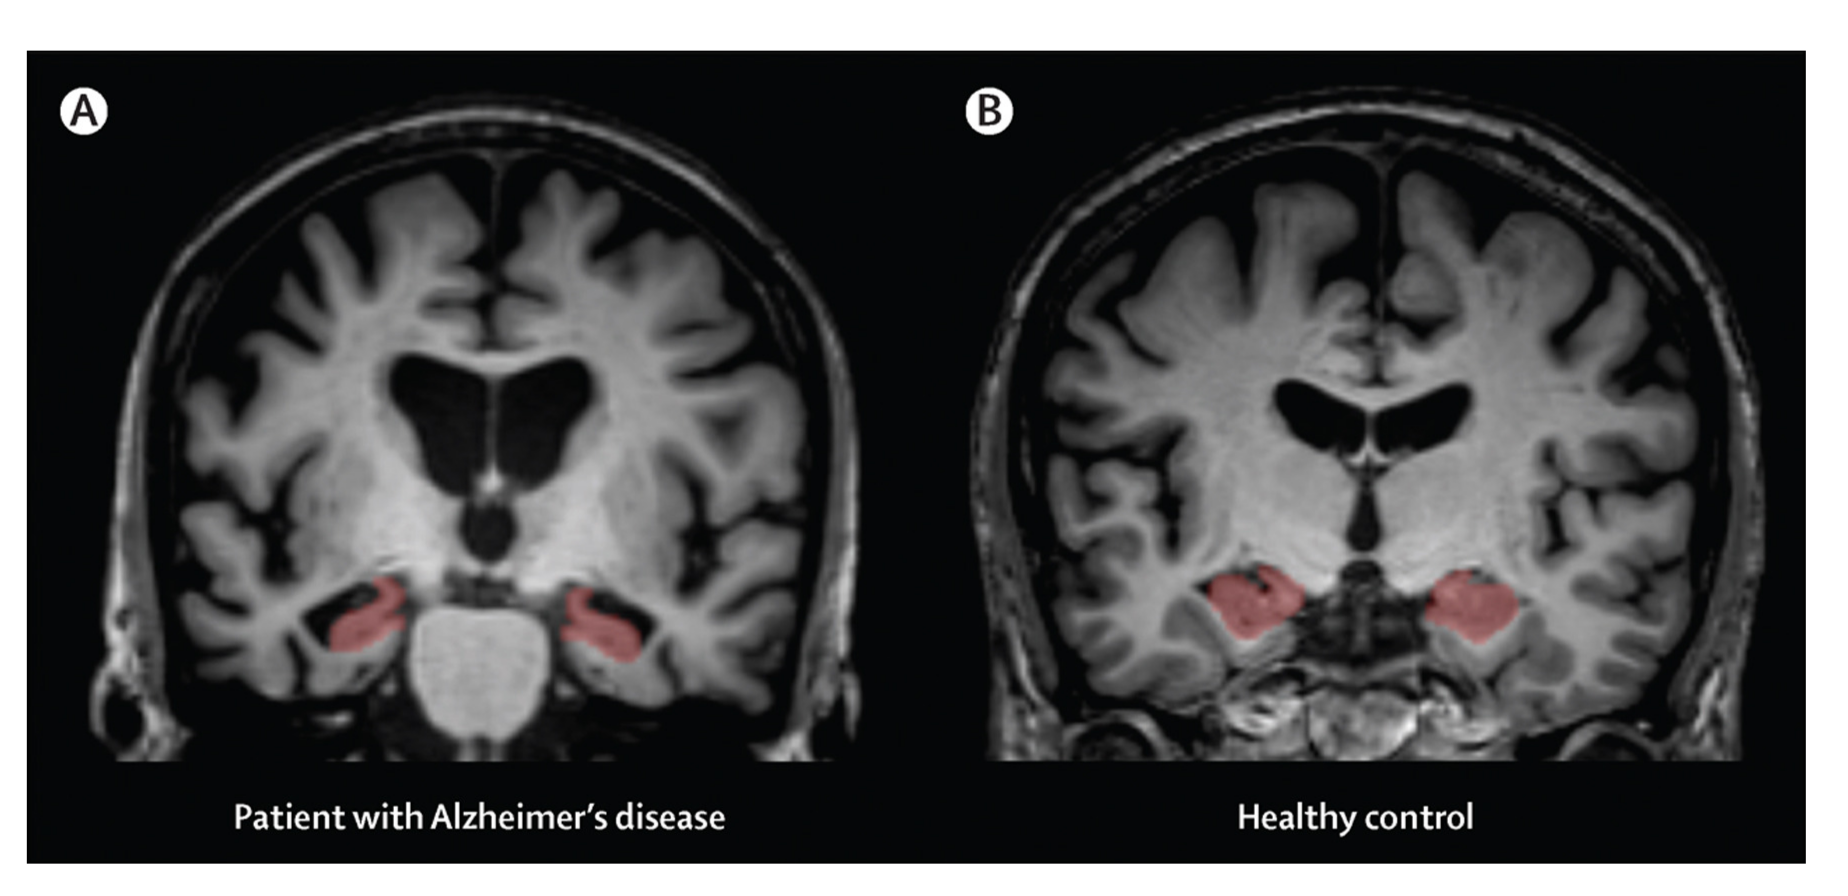

2.1.1. Neuroimaging Techniques